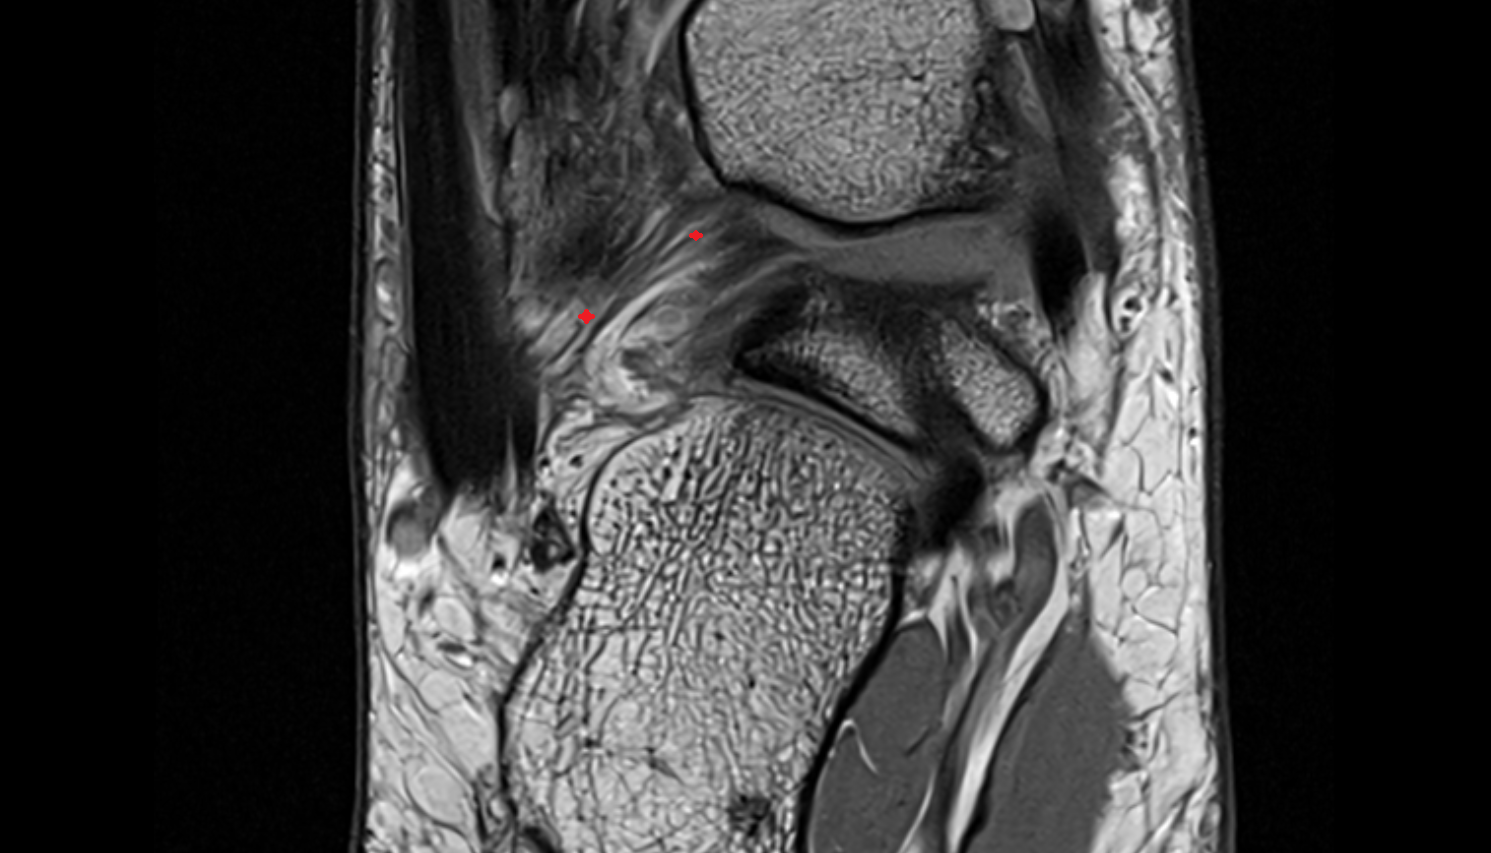

- Temporomandibular joint

- Mandibular condyle

- Mandibular fossa

- Articular disc of temporomandibular joint

- Articular eminence

- Superior retrodiscal layer

- Intermediate zone of articular disc

- Lateral temporomandibular ligament